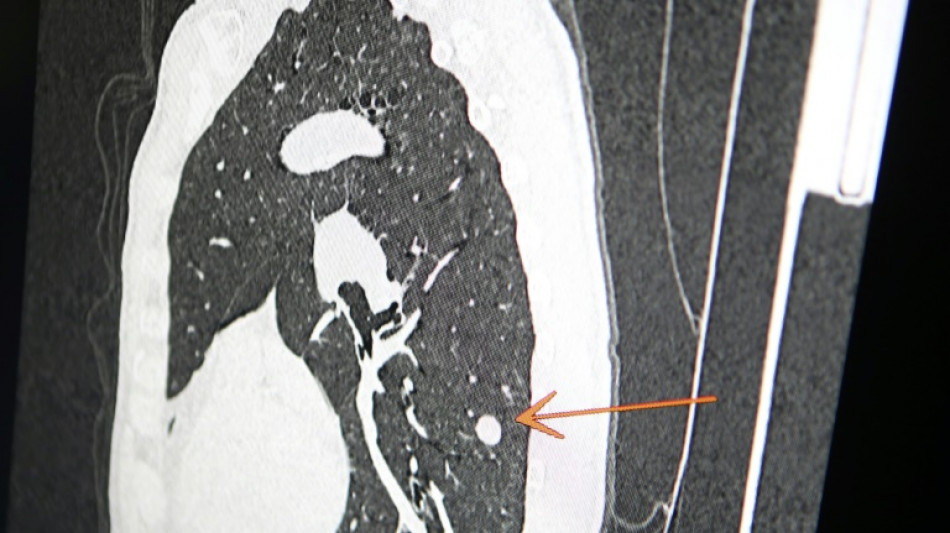

"Usted tiene cáncer", mensaje erróneo y aterrador a cientos de pacientes de una clínica en Inglaterra

Una clínica del norte de Inglaterra dio un gran susto a cientos de pacientes al enviar el mensaje "diagnóstico: cáncer de pulmón agresivo con metástasis" en lugar de sus buenos deseos de Navidad, informó el diario The Sun el jueves.

El 23 de diciembre a las 15H49, los pacientes de este centro de salud de Askern, cerca de la ciudad de Doncaster, recibieron un mensaje de texto en su teléfono informándoles de este diagnóstico, pidiéndoles que rellenaran los formularios correspondientes y concluyendo: "Gracias".

Según The Sun, entre los destinatarios del mensaje figuraba Chris Reed, un padre de familia de 57 años, que esperaba resultados de análisis para determinar si padecía cáncer de pulmón.